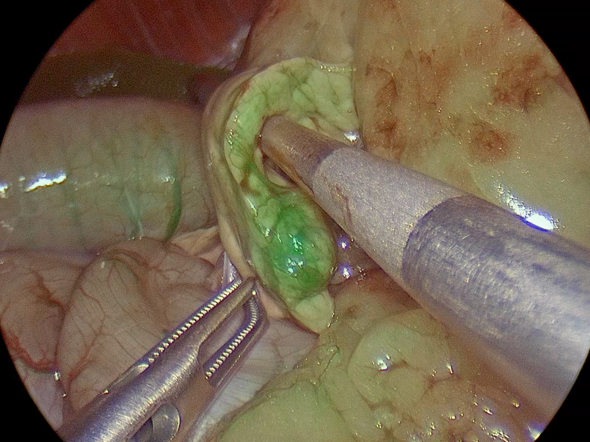

手術の様子

腹腔鏡カメラを用いて膵臓の確認、ICGを用いての膵臓腫瘤の辺縁の確認